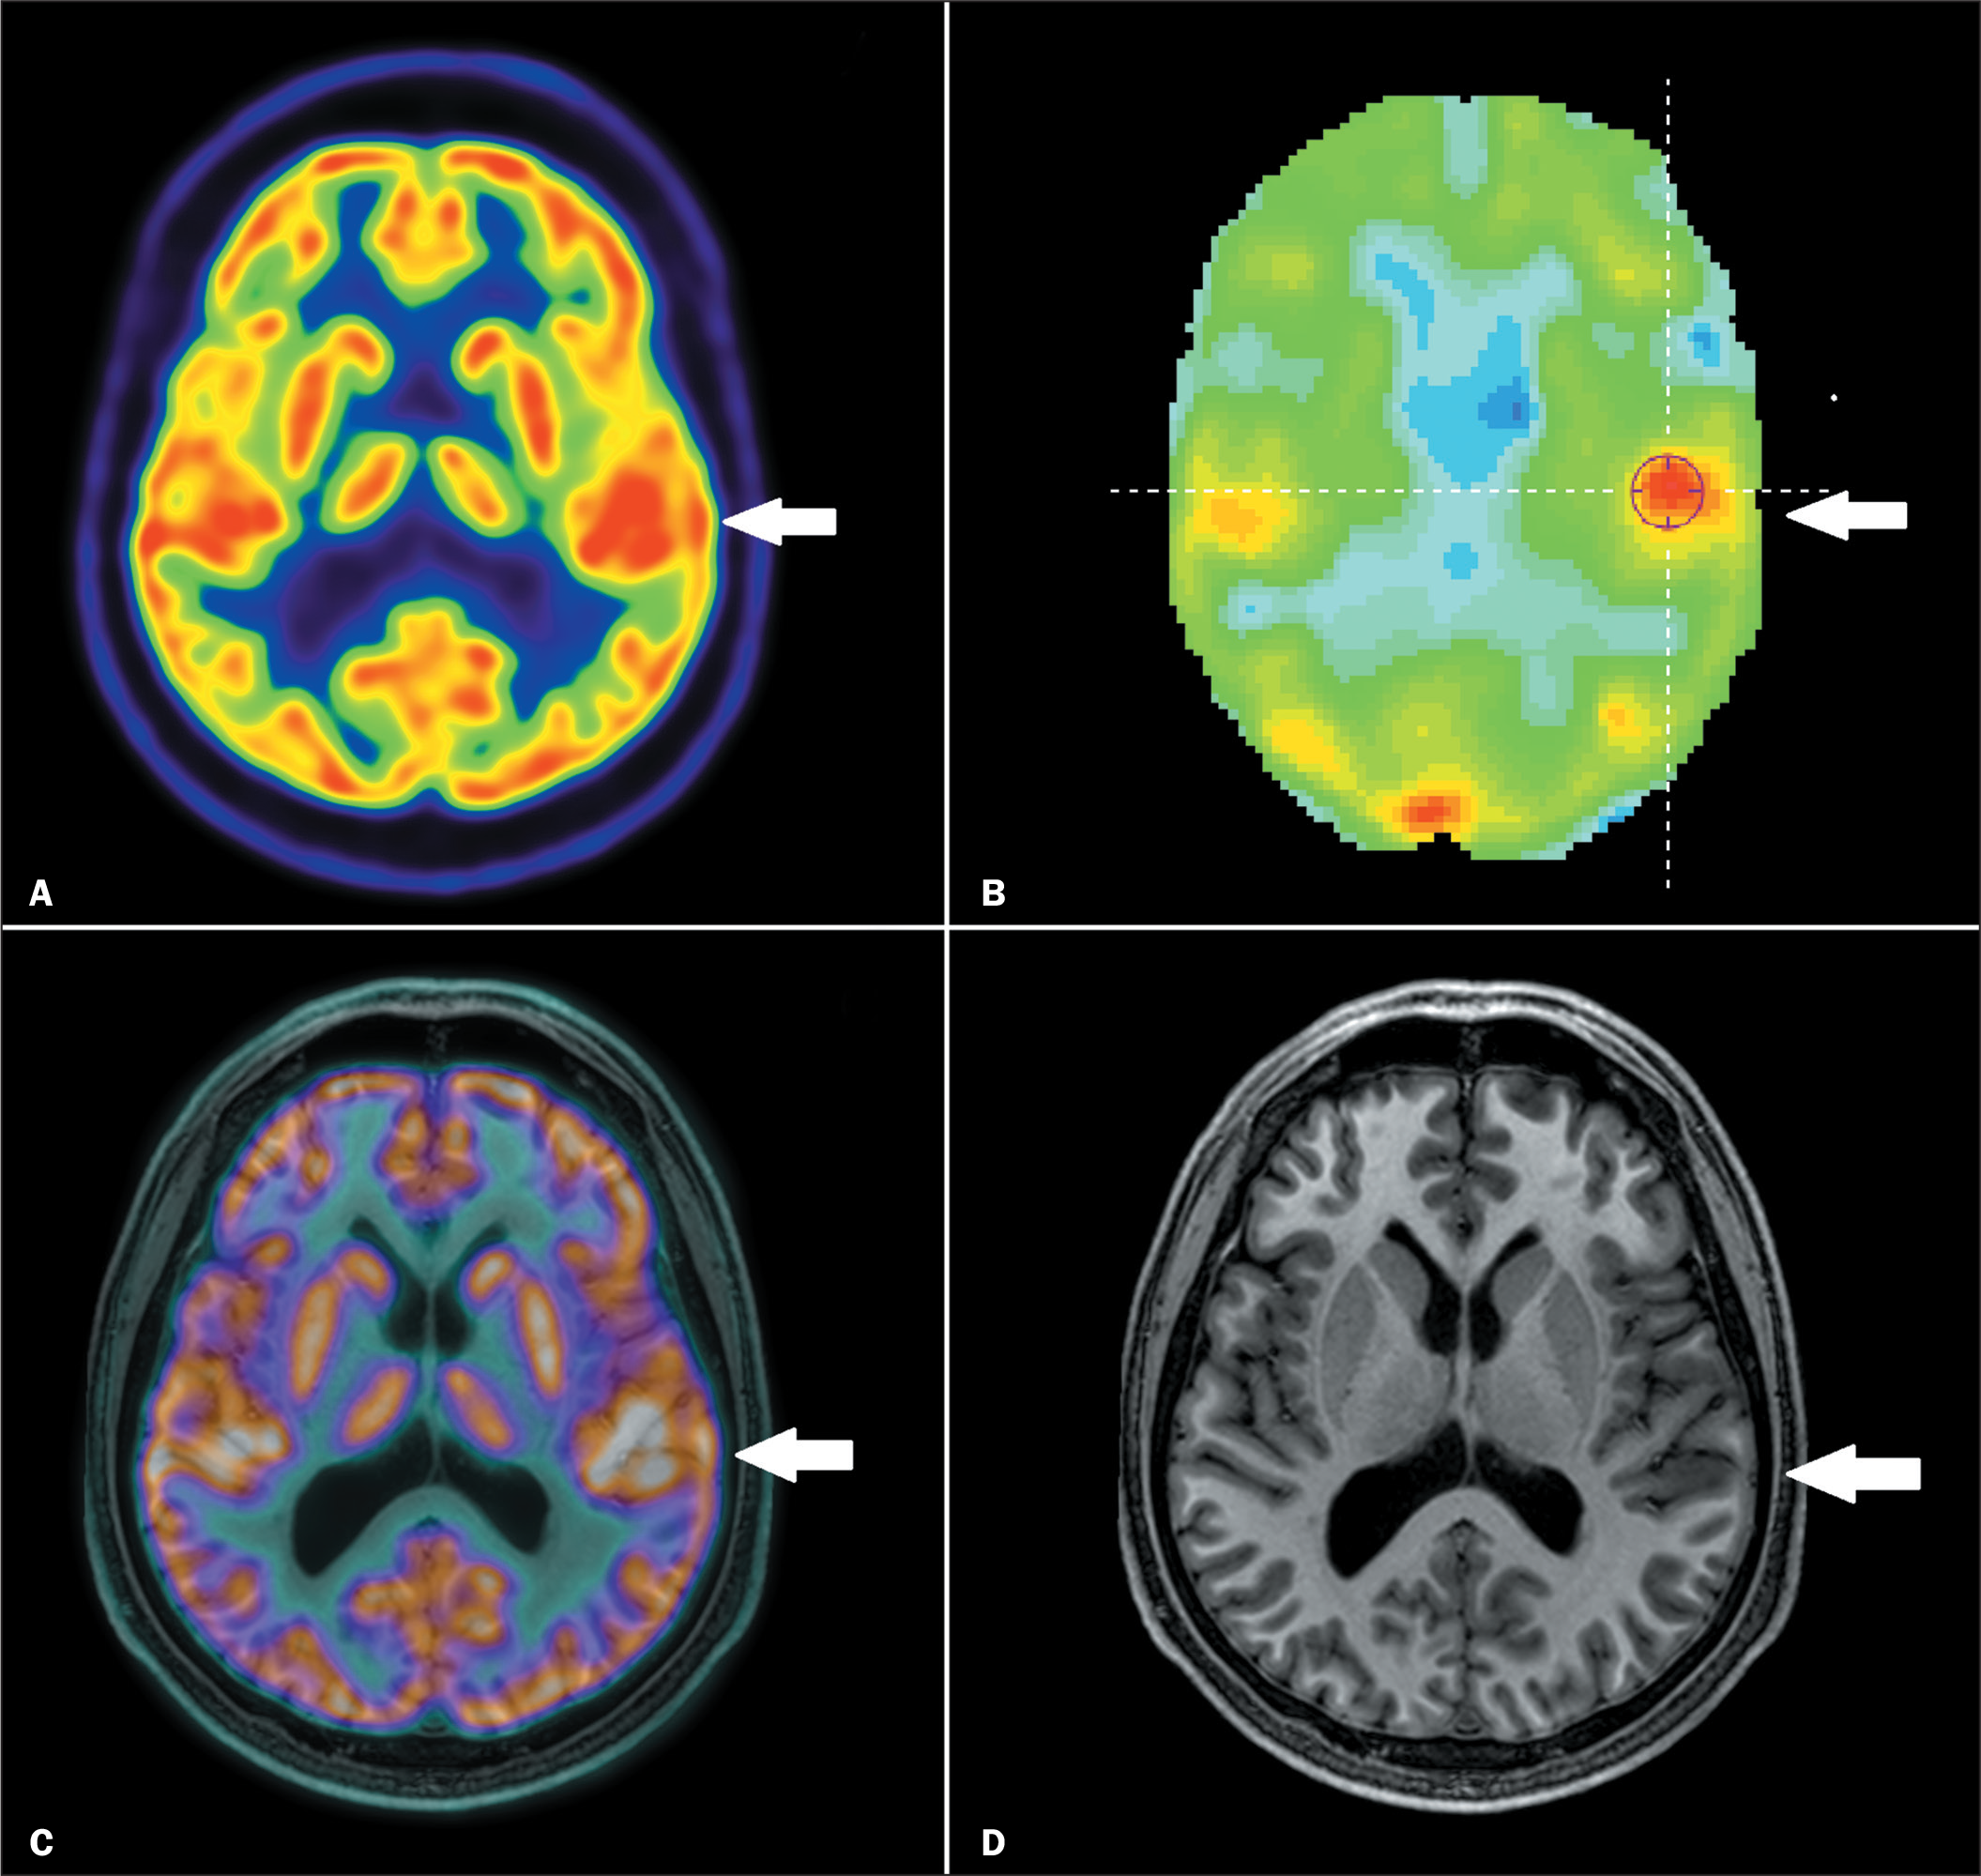

3. Diagnóstico e localização de epilepsia refratária

Muitos pacientes convivem com crises epilépticas que não respondem aos remédios. Para considerar cirurgia, é necessário localizar exatamente onde a crise começa no cérebro. O PET-CT, nesses casos, revela áreas de hipoatividade mesmo quando ressonância está normal. Pode mudar o destino do paciente, indicando a possibilidade de uma cirurgia resolutiva, por exemplo, melhorando a qualidade de vida.

Imagem de Interictal and postictal 18F-FDG PET/CT in epileptogenic zone localization.